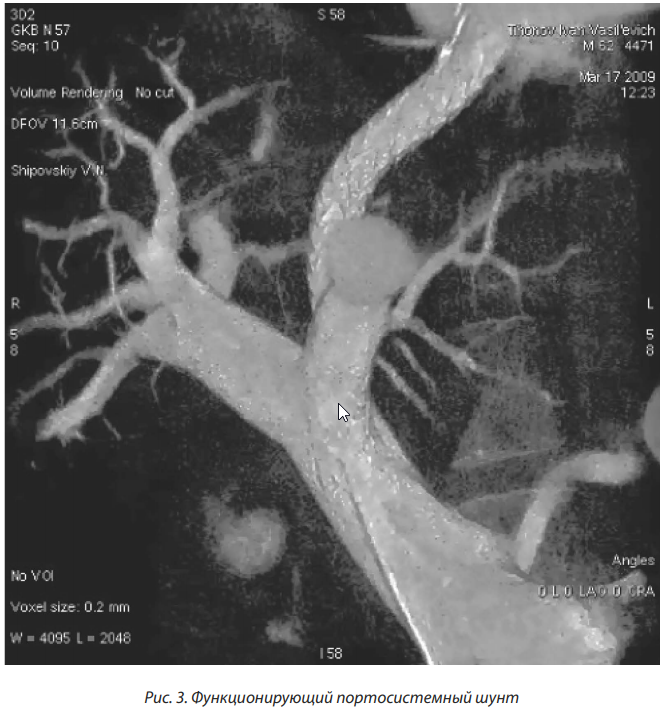

Большой интерес клиницистов вызвало внедрение во врачебную практику TIPS (transjugular intrahepatic portosystemic shunt), разработанного J. Rosch и соавторами в 1969 г. [14].

TIPS является малоинвазивной хирургической операцией, проводимой под контролем рентгеноскопии и включает в себя ряд эндоваскулярных процедур в определенной последовательности: после пункции яремной вены с помощью сосудистых стентов (голометалических или стент-графтов) формируется внутрипеченочное сообщение между крупными печеночными венами и ветвями воротной вены. Вследствие использования TIPS сохраняется гепатопетальний кровоток и осуществляется портальная декомпрессия (рис. 3).